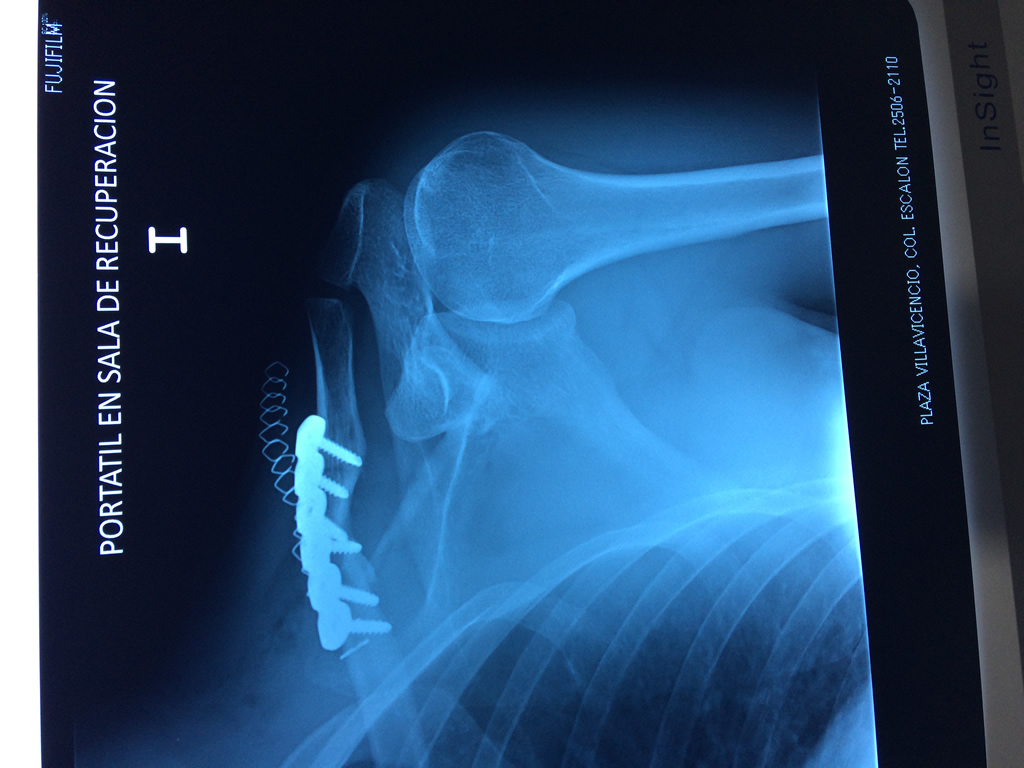

Cirugías de Codo - Clavícula